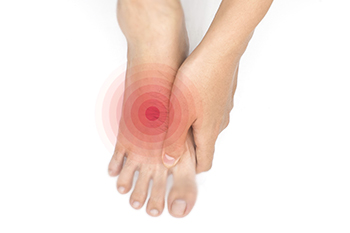

Foot arch pain can affect people of all ages and activity levels. The arch runs from the ball of the foot to the heel and acts as a natural shock absorber when walking, running, or standing. Pain in this area may feel dull, throbbing, burning, or sharp. It can develop from overuse, injuries, weakened tendons, stress fractures, or structural differences, such as very high or very flat arches. One frequent cause is inflammation of the plantar fascia, a thick band of tissue that supports the arch and helps maintain balance. Symptoms may include stiffness in the morning, swelling, or discomfort that worsens after long periods on the feet. A podiatrist can identify the source of arch pain through a physical exam, gait evaluation, and imaging tests. Treatment options include custom orthotics, bracing, or more advanced medical care to restore function and relieve discomfort. If you are experiencing pain in the arch of your foot, it is suggested that you make an appointment with a podiatrist for an exam, diagnosis, and treatment.

Foot Pain

Causes

Foot pain is a very broad condition that could be caused by one or more ailments. The most common include:

Diagnosis

To figure out the cause of foot pain, podiatrists utilize several different methods. This can range from simple visual inspections and sensation tests to X-rays and MRI scans. Prior medical history, family medical history, and any recent physical traumatic events will all be taken into consideration for a proper diagnosis.

Treatment

Treatment depends upon the cause of the foot pain. Whether it is resting, staying off the foot, or having surgery; podiatrists have a number of treatment options available for foot pain.